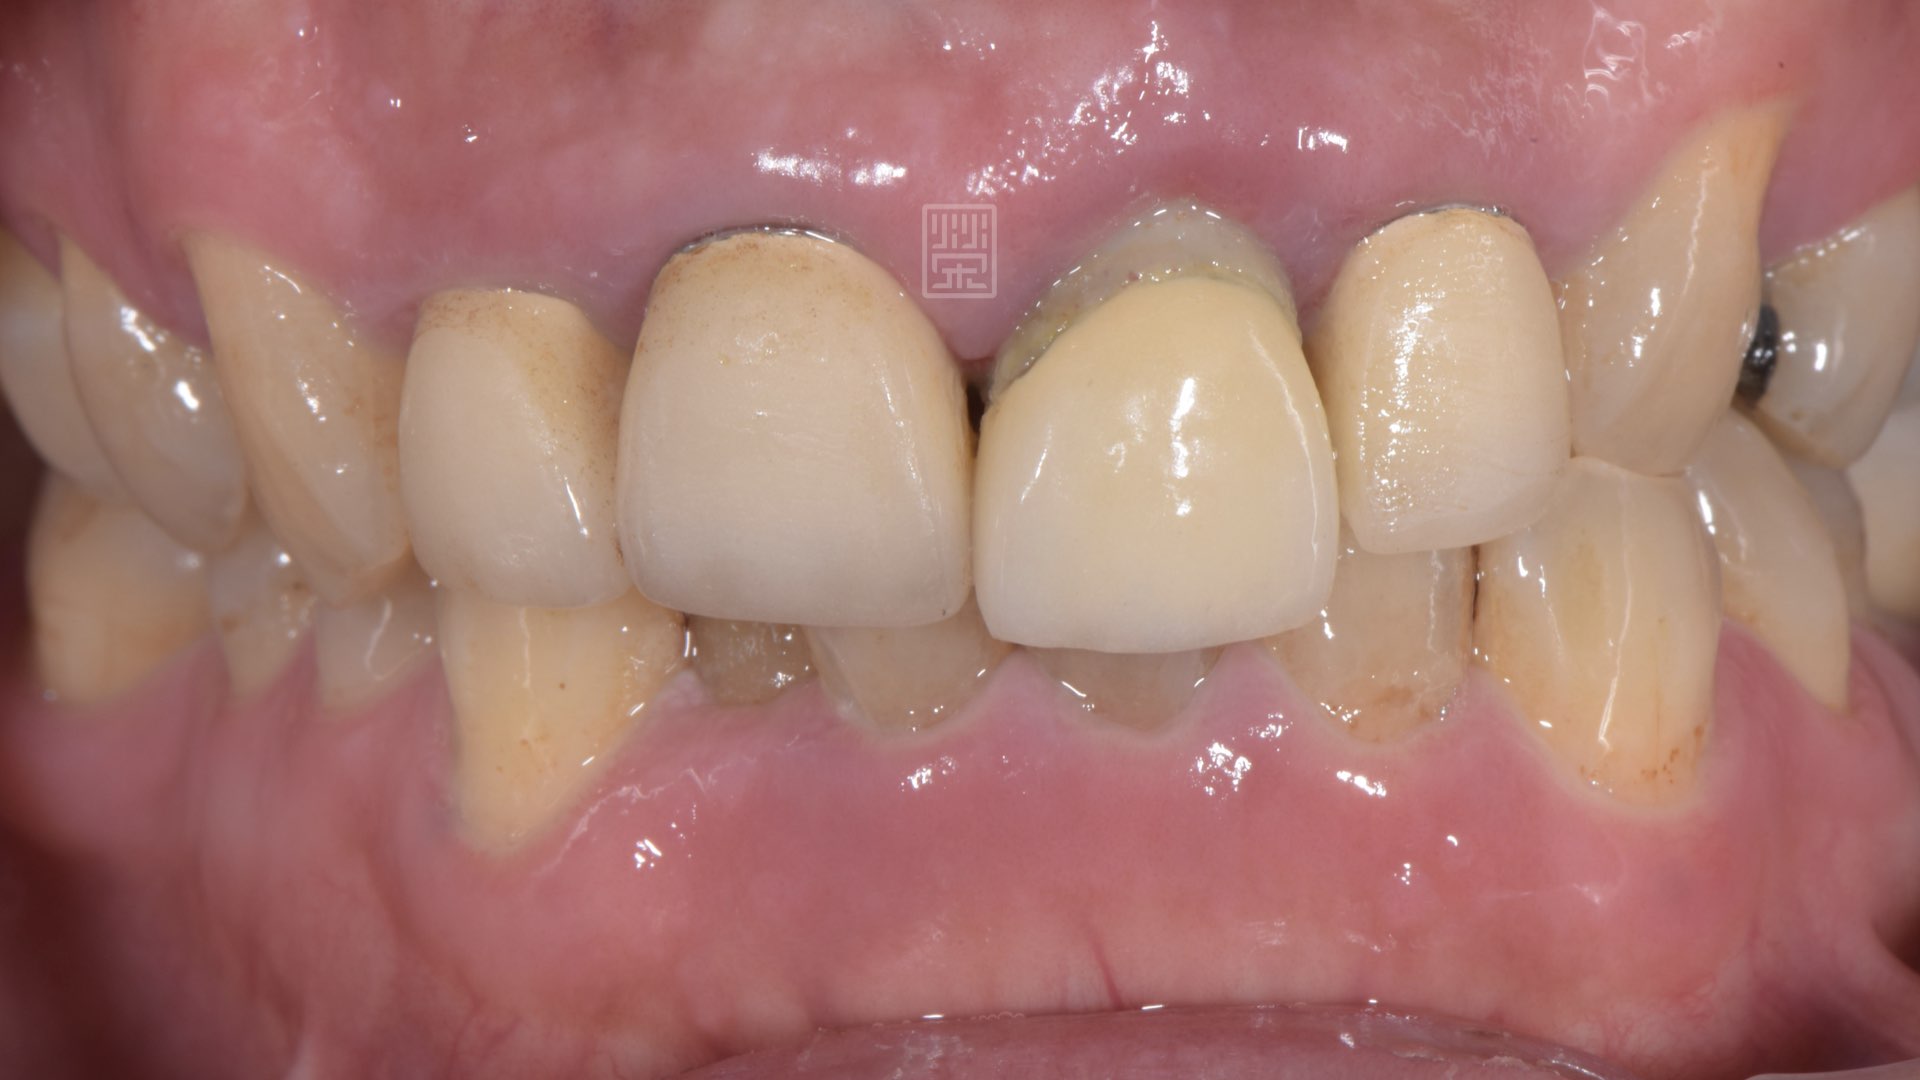

門齒斷裂造成掉下來

右側運動時,有犬齒導引保護,左側運動時,受力在門齒